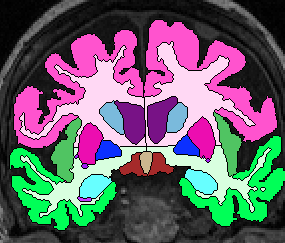

| Procedure for White Matter Parcellation: Frontal Lobe White Matter: Change "cerebral white matter" on every slice that has frontal lobe present on it to "frontal lobe white matter." This will, on some slices, for the time being, change some white matter that is actually temporal or parietal white matter to frontal lobe white matter. This will be corrected later on, however. |  (fig 1) |

| Temporal Lobe White Matter: Anteriorly, simply relabel the cerebral white matter in the temporal lobe as temporal lobe white matter (fig 2). When the white matter becomes continuous from the temporal lobe to the frontal, draw a horizontal line laterally from the inferior Insula, then extract the temporal white matter, leaving it unlabeled for the time being (fig 3- this image show it labeled, however). Once the frontal lobe gray matter superior to the amygdala is gone, draw a straight horizontal line from one fronto-temporal junction (lateral sulcus) to the other and extract the temporal white matter (fig 4).